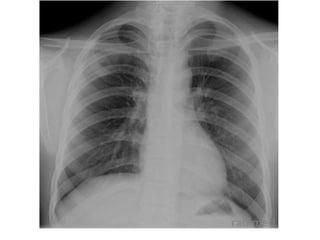

Inspiración

Rx Mal inspirada

Rx Bien inspirada